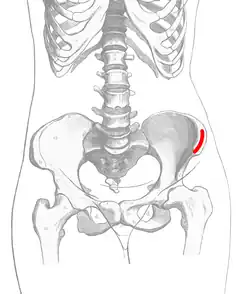

After creation of the pocket, but before suturing closed the gingiva a bone graft is placed into the bony defect. This is most commonly harvested from the anterior hip but can also be obtained from other sites, donor bone, or bioactive materials such as bone morphogenic proteins. Once packed the cleft is filled with bone material the gingiva is sutured closed to create a water tight closure between the mouth and the nose. [4]

Source of bone graft

The most common source of the bone graft is from the iliac crest,[6] harvested at the time of the cleft closure. Other sources such as the chin, and posterior iliac crest, or skull can also be used. Artificial grafts such as demineralized bone, recombinent bone morphogenic protein or a mix of harvested bone and artificial grafts have also been used. Insufficient data exists to show that one is beneficial over the other.[1]

The mouth wounds recover in 7–10 days with precautions for fluid only diet for 5 days, and not to increase pressure in the nose or sinuses for 2–3 weeks. Evidence that the bone graft is forming will be seen on x-ray at about 8 weeks. Movement of teeth into the graft can begin at 3 months once bone graft consolidation is seen on xray.[4] Recovery from the bone harvest will vary depending on the site (if harvested) with the anterior iliac crest being sore for 2–3 weeks.